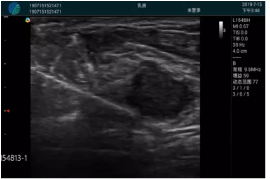

M20實(shí)時(shí)引導(dǎo):向包塊后方間隙注射利多卡因

清晰顯示腺體內(nèi)低回聲快影,邊界清晰,包膜較光滑

確定進(jìn)針路徑并實(shí)時(shí)監(jiān)測(cè)抽吸針與腫塊位置關(guān)系

抽吸針進(jìn)入腫塊內(nèi)部進(jìn)行旋切

抽吸過程中可見腫塊明顯縮小,并根據(jù)腫塊位置改變針道位置

抽吸旋切后再進(jìn)行超聲復(fù)查,原腫塊區(qū)域未見殘留組織及出血

超聲引導(dǎo)下抽吸旋切取出的腫塊組織